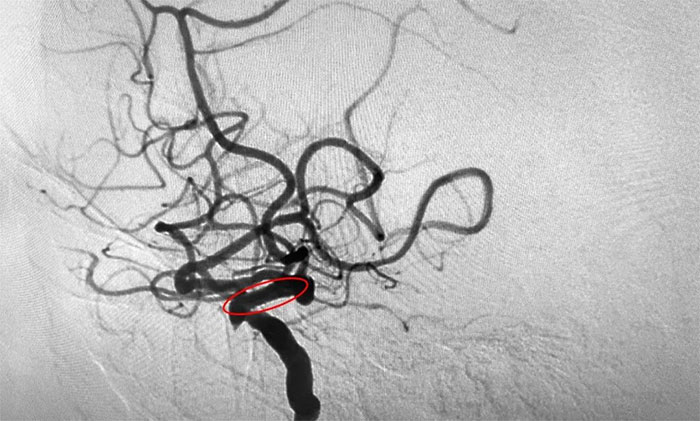

為進一步明確診斷并制定治療方案,周君主任與醫(yī)院學術副院長兼神經內科4A病區(qū)主任席剛明教授對患者病情開展了討論評估,由席教授為患者進行DSA全腦血管造影檢查,造影可見左頸內動脈巖骨水平段中度狹窄,左頸內動脈海綿竇段輕度狹窄,左頸內動脈眼動脈重度狹窄(狹窄程度約高于80%)。

▲ DSA檢查影像